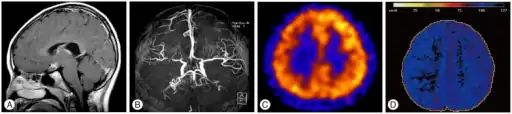

| T1-weighted MR image of moyamoya disease. Flow void in the basal ganglia is indicated by the arrow. | |

Often nuclear medicine studies such as SPECT (single photon emission computerized tomography) are used to demonstrate the decreased blood and oxygen supply to areas of the brain involved with moyamoya disease. Conventional angiography provides the conclusive diagnosis of moyamoya disease in most cases and should be performed before any surgical considerations.

There is also research that has shown that certain radiographic biomarkers that lead to the diagnosis of moyamoya disease have been identified. The specific radiographic markers are now considered an acceptable key component to moyamoya disease and have been added to the International Classification of Diseases (ICD). These biomarkers of moyamoya are "stenosis of the distal ICA's up to and including the bifurcation, along with segments of the proximal ACA and MCA...dilated basal collateral vessels must be present" [19] Some other common findings that have not been added to the classification index of those with moyamoya disease which are found using radiography involve very distinct changes in the vessels of the brain. These changes include newly formed vessels made to compensate for another change noted, ischemia and cerebrovascular reserve, both found on MRI. Functional changes include evidence of ischemia in vessels of the brain (ICA, ACA, MCA, specifically). It is important to also note that the radiographic biomarkers, in order to be classified as moyamoya disease, all findings must be bilateral. If this is not the case and the findings are unilateral, it is diagnosed as moyamoya syndrome.[19]